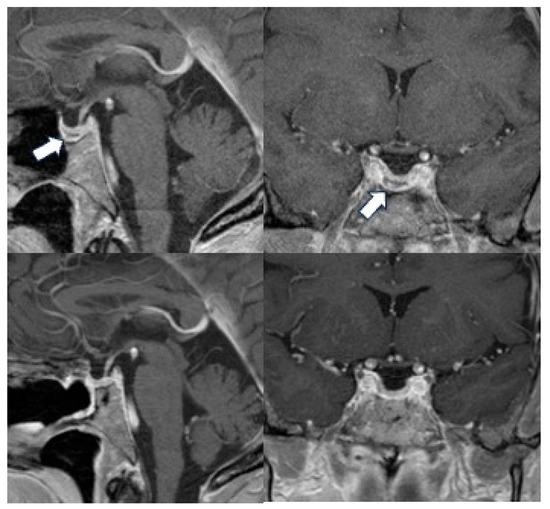

Reassessing Routine Postoperative Imaging in Acromegaly: Insights from a Cohort with Biochemical Remission

Surgeries 2026, 7(2), 43; https://doi.org/10.3390/surgeries7020043 - 26 Mar 2026

Background: Postoperative evaluation for growth hormone-producing pituitary tumors entails assessing remission via biochemical markers alongside MRI to detect residual tumors. While postoperative imaging provides important anatomical information regarding potential residual tumor, it is reasonable to ask if imaging offers largely redundant data

Background: Postoperative evaluation for growth hormone-producing pituitary tumors entails assessing remission via biochemical markers alongside MRI to detect residual tumors. While postoperative imaging provides important anatomical information regarding potential residual tumor, it is reasonable to ask if imaging offers largely redundant data when biochemical remission is already established. This study aimed to determine the clinical utility of post-surgical surveillance imaging in patients who achieved biochemical remission with normal age- and sex-matched IGF-1 at ~3 months postoperatively. Furthermore, we sought to evaluate the long-term durability of biochemical control in this patient subset. Methods: We conducted a retrospective analysis on patients who underwent endoscopic endonasal approach surgery for acromegaly and had a minimum of 3 years of follow-up clinical, biochemical and imaging data. Results: In total, 15 of 28 patients (54%) achieved initial biochemical remission and had a 100% sustained remission rate during the follow-up period of 3–14 years, underscoring the importance of surgical radicality for achieving durable remission. Conclusions: Our findings suggest that for patients who achieved biochemical remission following transsphenoidal surgery for acromegaly, routine postoperative imaging provides negligible additional diagnostic information from an endocrinological perspective. As such, we propose that no further postoperative imaging is needed for patients in clinical and biochemical remission. This approach offers a significant reduction in the clinical burden and healthcare costs for patients associated with long-term management of their disease.